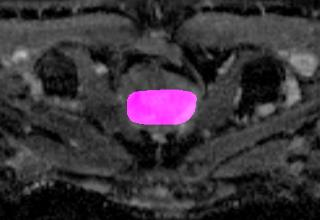

Weakly Supervised Semantic Segmentation (WSSS) relying only on image-level supervision is a promising approach to deal with the need for Segmentation networks, especially for generating a large number of pixel-wise masks in a given dataset. However, most state-of-the-art image-level WSSS techniques lack an understanding of the geometric features embedded in the images since the network cannot derive any object boundary information from just image-level labels. We define a boundary here as the line separating an object and its background, or two different objects. To address this drawback, we are proposing our novel ReFit framework, which deploys state-of-the-art class activation maps combined with various post-processing techniques in order to achieve fine-grained higher-accuracy segmentation masks. To achieve this, we investigate a state-of-the-art unsupervised segmentation network that can be used to construct a boundary map, which enables ReFit to predict object locations with sharper boundaries. By applying our method to WSSS predictions, we achieved up to 10% improvement over the current state-of-the-art WSSS methods for medical imaging. The framework is open-source, to ensure that our results are reproducible, and accessible online at https://github.com/bharathprabakaran/ReFit.